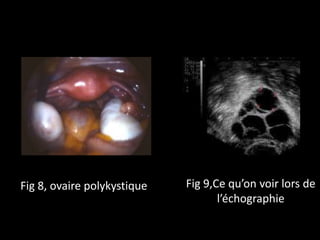

Fig 8, ovaire polykystique Fig 9,Ce qu’on voir lors de

l’échographie

Fig 8, ovairepolykystique Fig 9,Ce qu’on voir lors de l’échographie

♀Chez la plupart des patientes, on observe à

l’ultrasonographie l’image typique de follicules

arrangés en collier de perles à proximité de la

surface des ovaires.